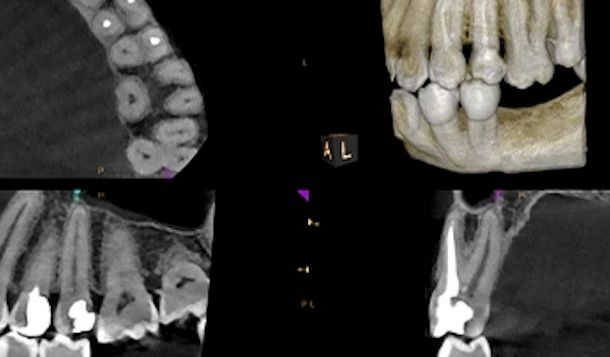

¿Y si la altura y el grosor de mi hueso maxilar son muy reducidos?

• En esos casos existe la posibilidad de realizar un injerto de hueso, es decir añadir biomateriales para aumentar la cantidad de hueso disponible. También podemos realizar una técnica de elevación de seno maxilar si la altura de hueso en las zonas posteriores del maxilar superior es insuficiente.

• Dependiendo de la calidad del hueso y de la estabilidad del implante en el momento de la cirugía, habrá que esperar más o menos para la colocación de la prótesis. En general serán alrededor de 3 meses los que haya que esperar para que se produzca la integración del implante con el hueso.